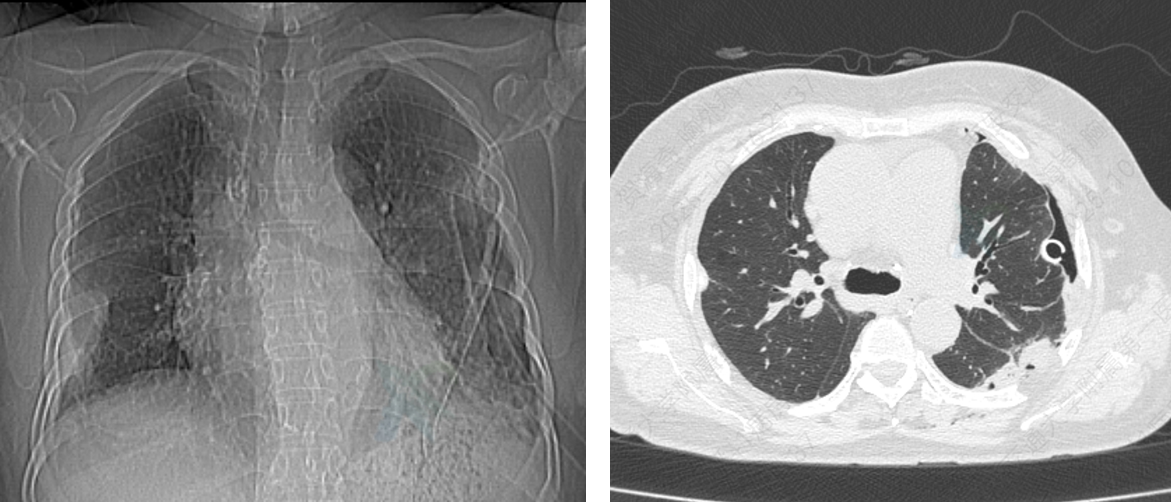

图3 术后CT检查显示左肺已完全复张